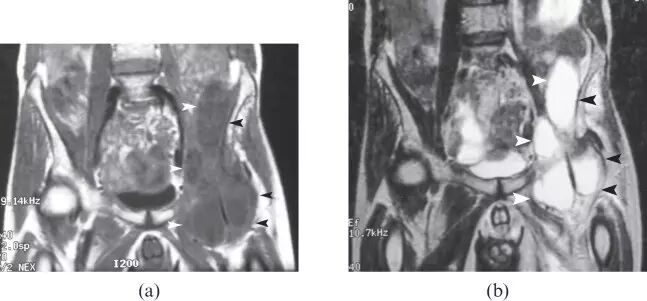

![]()

图21.59岁的男性,脓肿形成的肌萎缩继续直接对髋部刺激,并伴有左大腿发烧和不适的疼痛。 (a)冠状T1加权的MR图像显示大的、香肠状流体聚集在左髂腰肌和髂骨肌(箭头),从骨盆延伸到髋部。 (b)对应的冠状T2加权的MR图像显示邻近髂骨的翼并且在左侧的髋关节之前的多个、广泛的高信号强度---脓肿(箭头)。 脓肿材料的培养物显示金黄色葡萄球菌。